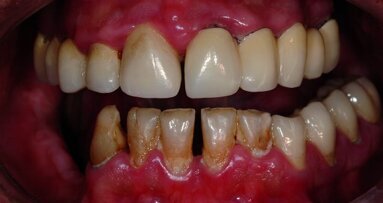

Il s’agit d’un patient, ancien fumeur, âgé de 51 ans au début du traitement. Ce patient présente une hypertension artérielle stabilisée, il est sous Kardégic® pour un infarctus en 2005. Ce patient souhaite une réhabilitation fixe au maxillaire. Ses motivations sont à la fois d’ordre fonctionnel et esthétique (Figs. 1a et 1b).

L’état parodontal des dents restantes ne permet pas d’envisager leur conservation. Toutes les dents maxillaires sont extraites de manière atraumatique, les alvéoles soigneusement curetées et une prothèse maxillaire amovible complète est mise en place le jour même. Après une période de cicatrisation, un dentascan permet d’évaluer le volume osseux disponible. Cet examen confirme une résorption osseuse importante dans les secteurs postérieurs du maxillaire (Figs. 2a–c) : SA4 dans la classification de C. Misch. Le volume osseux étant < 5 mm, la pose des implants sera différée de 5 à 6 mois après les comblements sinusiens, ceci afin d’obtenir une stabilité primaire suffisante.